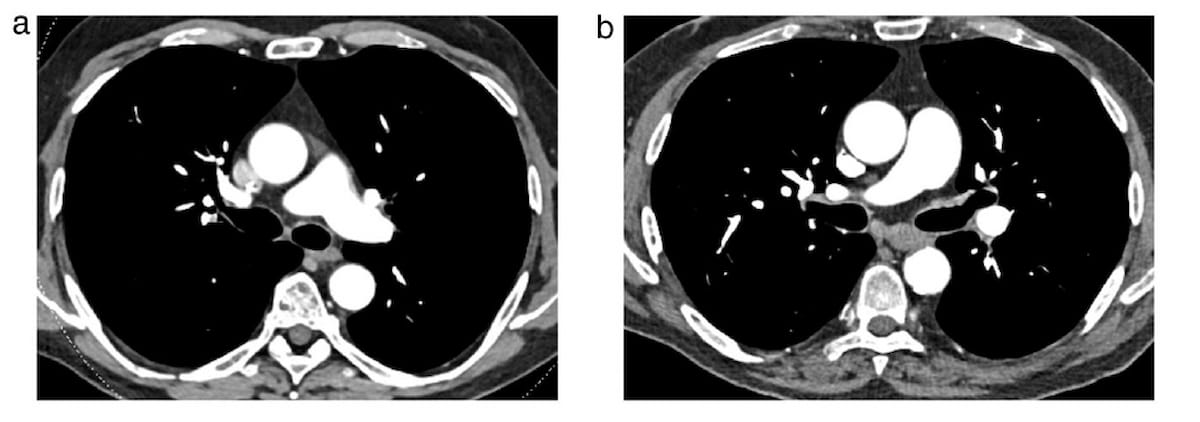

The artificial intelligence (AI) modalities CINA-iPE and CINA-ASPECTS may facilitate improved detection of incidental pulmonary embolism and stroke evaluation, respectively, based on computed tomography (CT) scans.